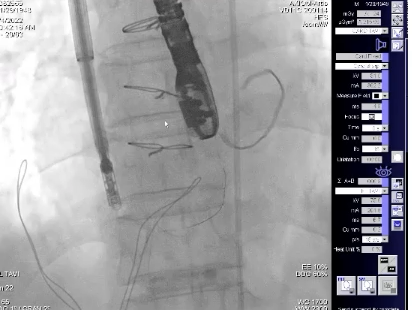

手术过程

患者全麻后,右侧颈静脉穿刺,将K-Clip®输送系统送达右心房内。在超声医生指引下,对K-Clip®的输送系统进行调姿,将K-Clip®锚定到位。

到位后,将K-Clip®夹持臂打开到最大,对目标瓣环位置进行夹合。判定三尖瓣反流减少程度满意后,解离夹合件,退出输送系统。

术后评估三尖瓣反流程度从重度反流(4+)下降为轻中度(1~2+)反流,评估冠脉血流通畅,令人满意,即结束手术。手术在1小时内完成,器械操作时间30分钟。